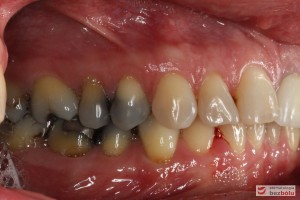

Do naszej placówki zgłosiła się starannie planująca swoje działania Europejka, mieszkająca na stałe w Kotlinie Jeleniogórskiej. Jej oczekiwania dotyczyły bardzo metodycznie zaplanowanego planu leczenia. Celem jaki postawiła przed naszym zespołem lekarzy było wyeliminowanie wszystkich wątpliwych i nierokujących wypełnień, a także poprawa estetyki w zakresie lewego siekacza centralnego w szczęce. Został rozpisany blisko dwuletni plan wymiany zużytych i nieszczelnych wypełnień amalgamatowych i kompozytowych. Zaplanowano również przygotowanie endodontyczne wybranych zębów w szczęce i żuchwie, a także zaopatrzenie w inlay’e porcelanowe i korony ceramiczne wykonane w systemie e-max.